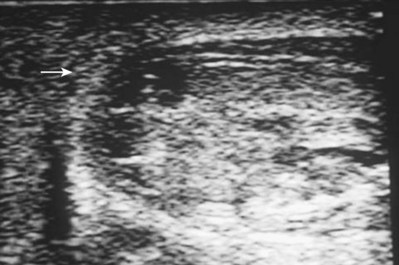

Ultrasonography can be helpful to assess the integrity and vascularity of the testis in equivocal cases. Ultrasonography is rapid, readily available, and noninvasive. Because it may be operator dependent, false-positive and false-negative studies range from 56% to 94% (Fournier et al, 1989; Corrales et al, 1993; Herbener, 1996; Dreitlein et al, 2001). Ultrasound findings suggestive of testicular fracture include a heterogeneous echo pattern of the testicular parenchyma and disruption of the tunica albuginea (Micallef et al, 2001; Buckley and McAninch, 2006) (Fig. 88–4). Although ultrasonography may assist in detection of testicular fracture or hematoma (Guichard et al, 2008), a normal or equivocal ultrasound study should not delay surgical exploration when physical examination findings suggest testicular damage; definitive diagnosis is often made in the operating room. Although MRI may effectively demonstrate testicular integrity, its widespread use is not the norm because of expense, limited availability, and potential delay in definitive surgical care of the patient (Serra et al, 1998; Muglia et al, 2002; Kim et al, 2009).

Figure 88–4 Ultrasound examination demonstrates hypoechoic intratesticular areas (arrow) consistent with testicular rupture sustained by blunt trauma. Scrotal exploration revealed large hematocele and exposed seminiferous tubules.